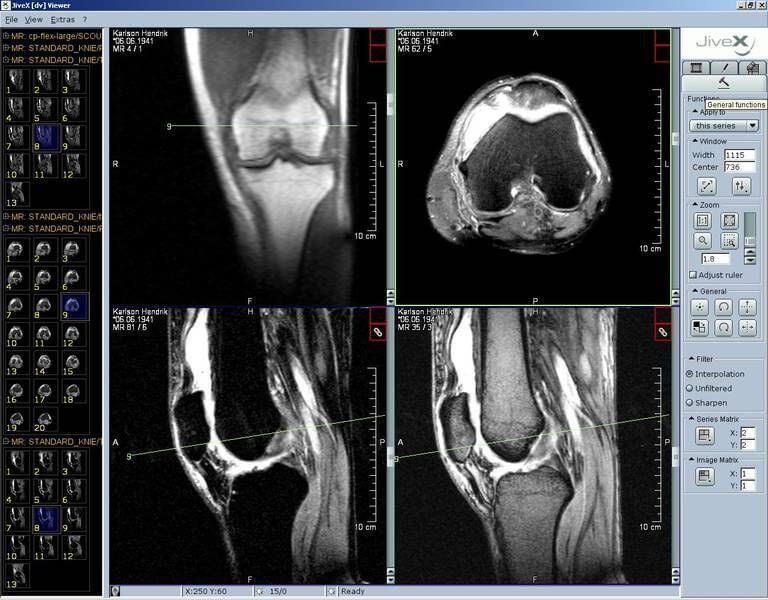

This is the free version of the paid software JiveX Review Client, and is meant to be used in educational and research activities. The viewer supports not only radiology images in the DICOM format, but also other medical data such as ECGs. The freeware does not allow users access to a PACS server or technical support. Although the viewer improves workflow, advanced manipulation of images is not possible with the free version.

| 13. | JiveX DICOM Viewer | Windows | PACS integration in paid version only | N | N | N | N.A. | N.A. | N.A. | Free version does not allow storage and support |